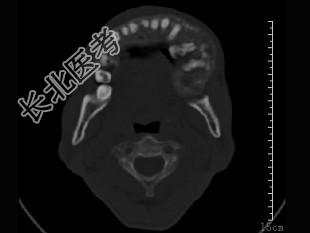

- 单项选择题女,23岁, 左颌部疼痛肿胀一年余,近来加重, CT表现如图,最可能的诊断是 ( )

A、造釉细胞瘤

B、混合性牙瘤

C、中央性颌骨癌

D、颌骨血管瘤

E、牙龈癌